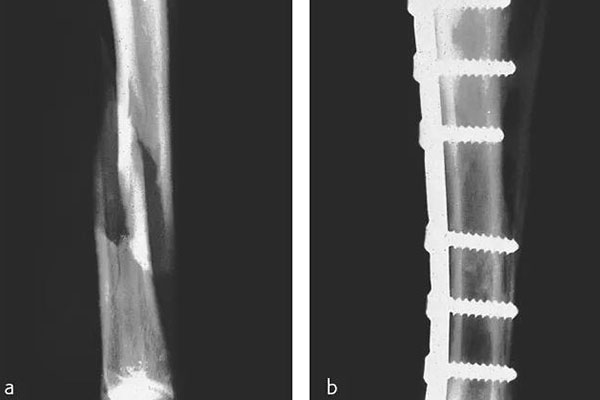

那在檢測(cè)的時(shí)候還需要看到植入物的情況,但由CFPEEK復(fù)合材料制成的零件通常具有放射透性,幾乎無法通過X射線檢測(cè)。就通過添加諸如鉭絲之類的X射線散射材料,可以使植入物變得可見??梢钥聪聢D展示了一個(gè)固定骨折骨頭的骨愈合板??梢钥闯觯ㄟ^設(shè)計(jì)已對(duì)放射密度進(jìn)行了定制,以便在盡量減少對(duì)骨折部位遮擋的同時(shí)可視化組件。重要的是,實(shí)現(xiàn)X射線可見性的同時(shí)也能保持清晰的MRI圖像。